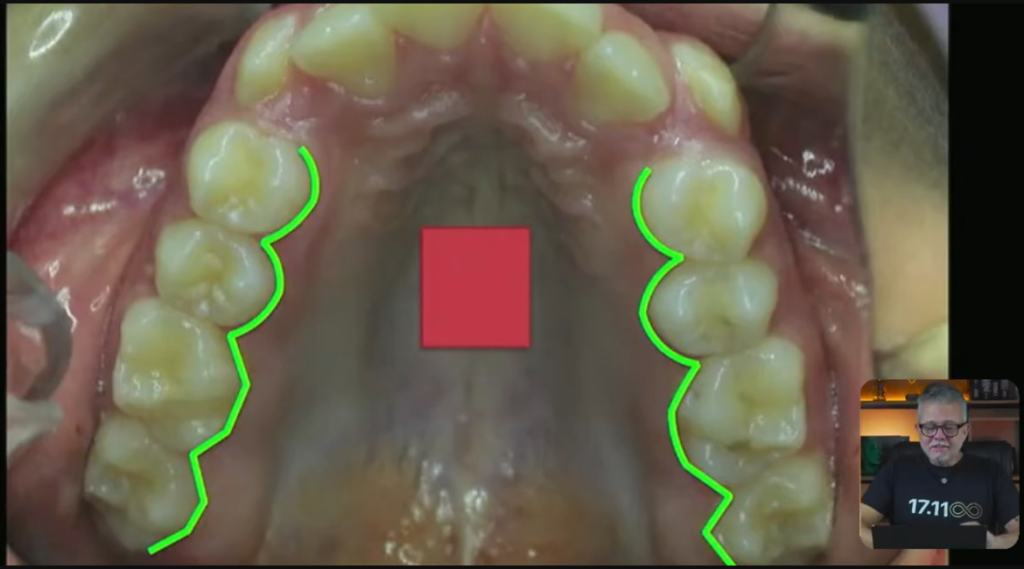

Imagina que é um expansor:

Esse expansor aqui, ele faz uma força nos pré e também nos pré do outro lado:

Então, esse verdinho que você está vendo aqui, ele vai fazer esse tipo de movimento:

Esses pré vão expandir desse jeito que você acabou de ver. Muito mais na região dos pré do que dos molares, tá?

Vai acontecer uma expansão nessa região.

E na ortopedia, a gente também coloca um negócio chamado mola frontal. Ela encosta no lateral e ela leva esse lateralzinho para vestibular:

Eu posso muito bem pegar o diagrama ortodôntico do meu paciente e fazer com que esse diagrama fique mais ou menos com esse formato: